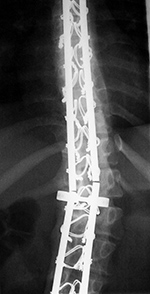

| 75-year old woman with expandable corpectomy cage used to treat a comminuted T11 compression fracture (left and center images). A follow-up study 3 months after cage placement (right image) shows cage shift probably from increased fracture compression. The cage remained stable at that point. |